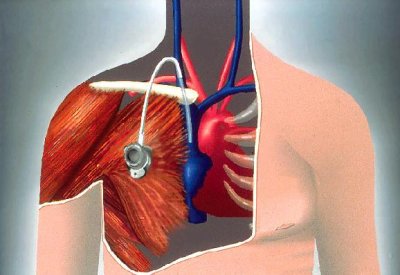

Recommandation Chambre Implantable 2020

Les traitements du cancer du pancréas (mis à jour en 2020). Chambre implantable perfusable / cci : Pour compléter les […]